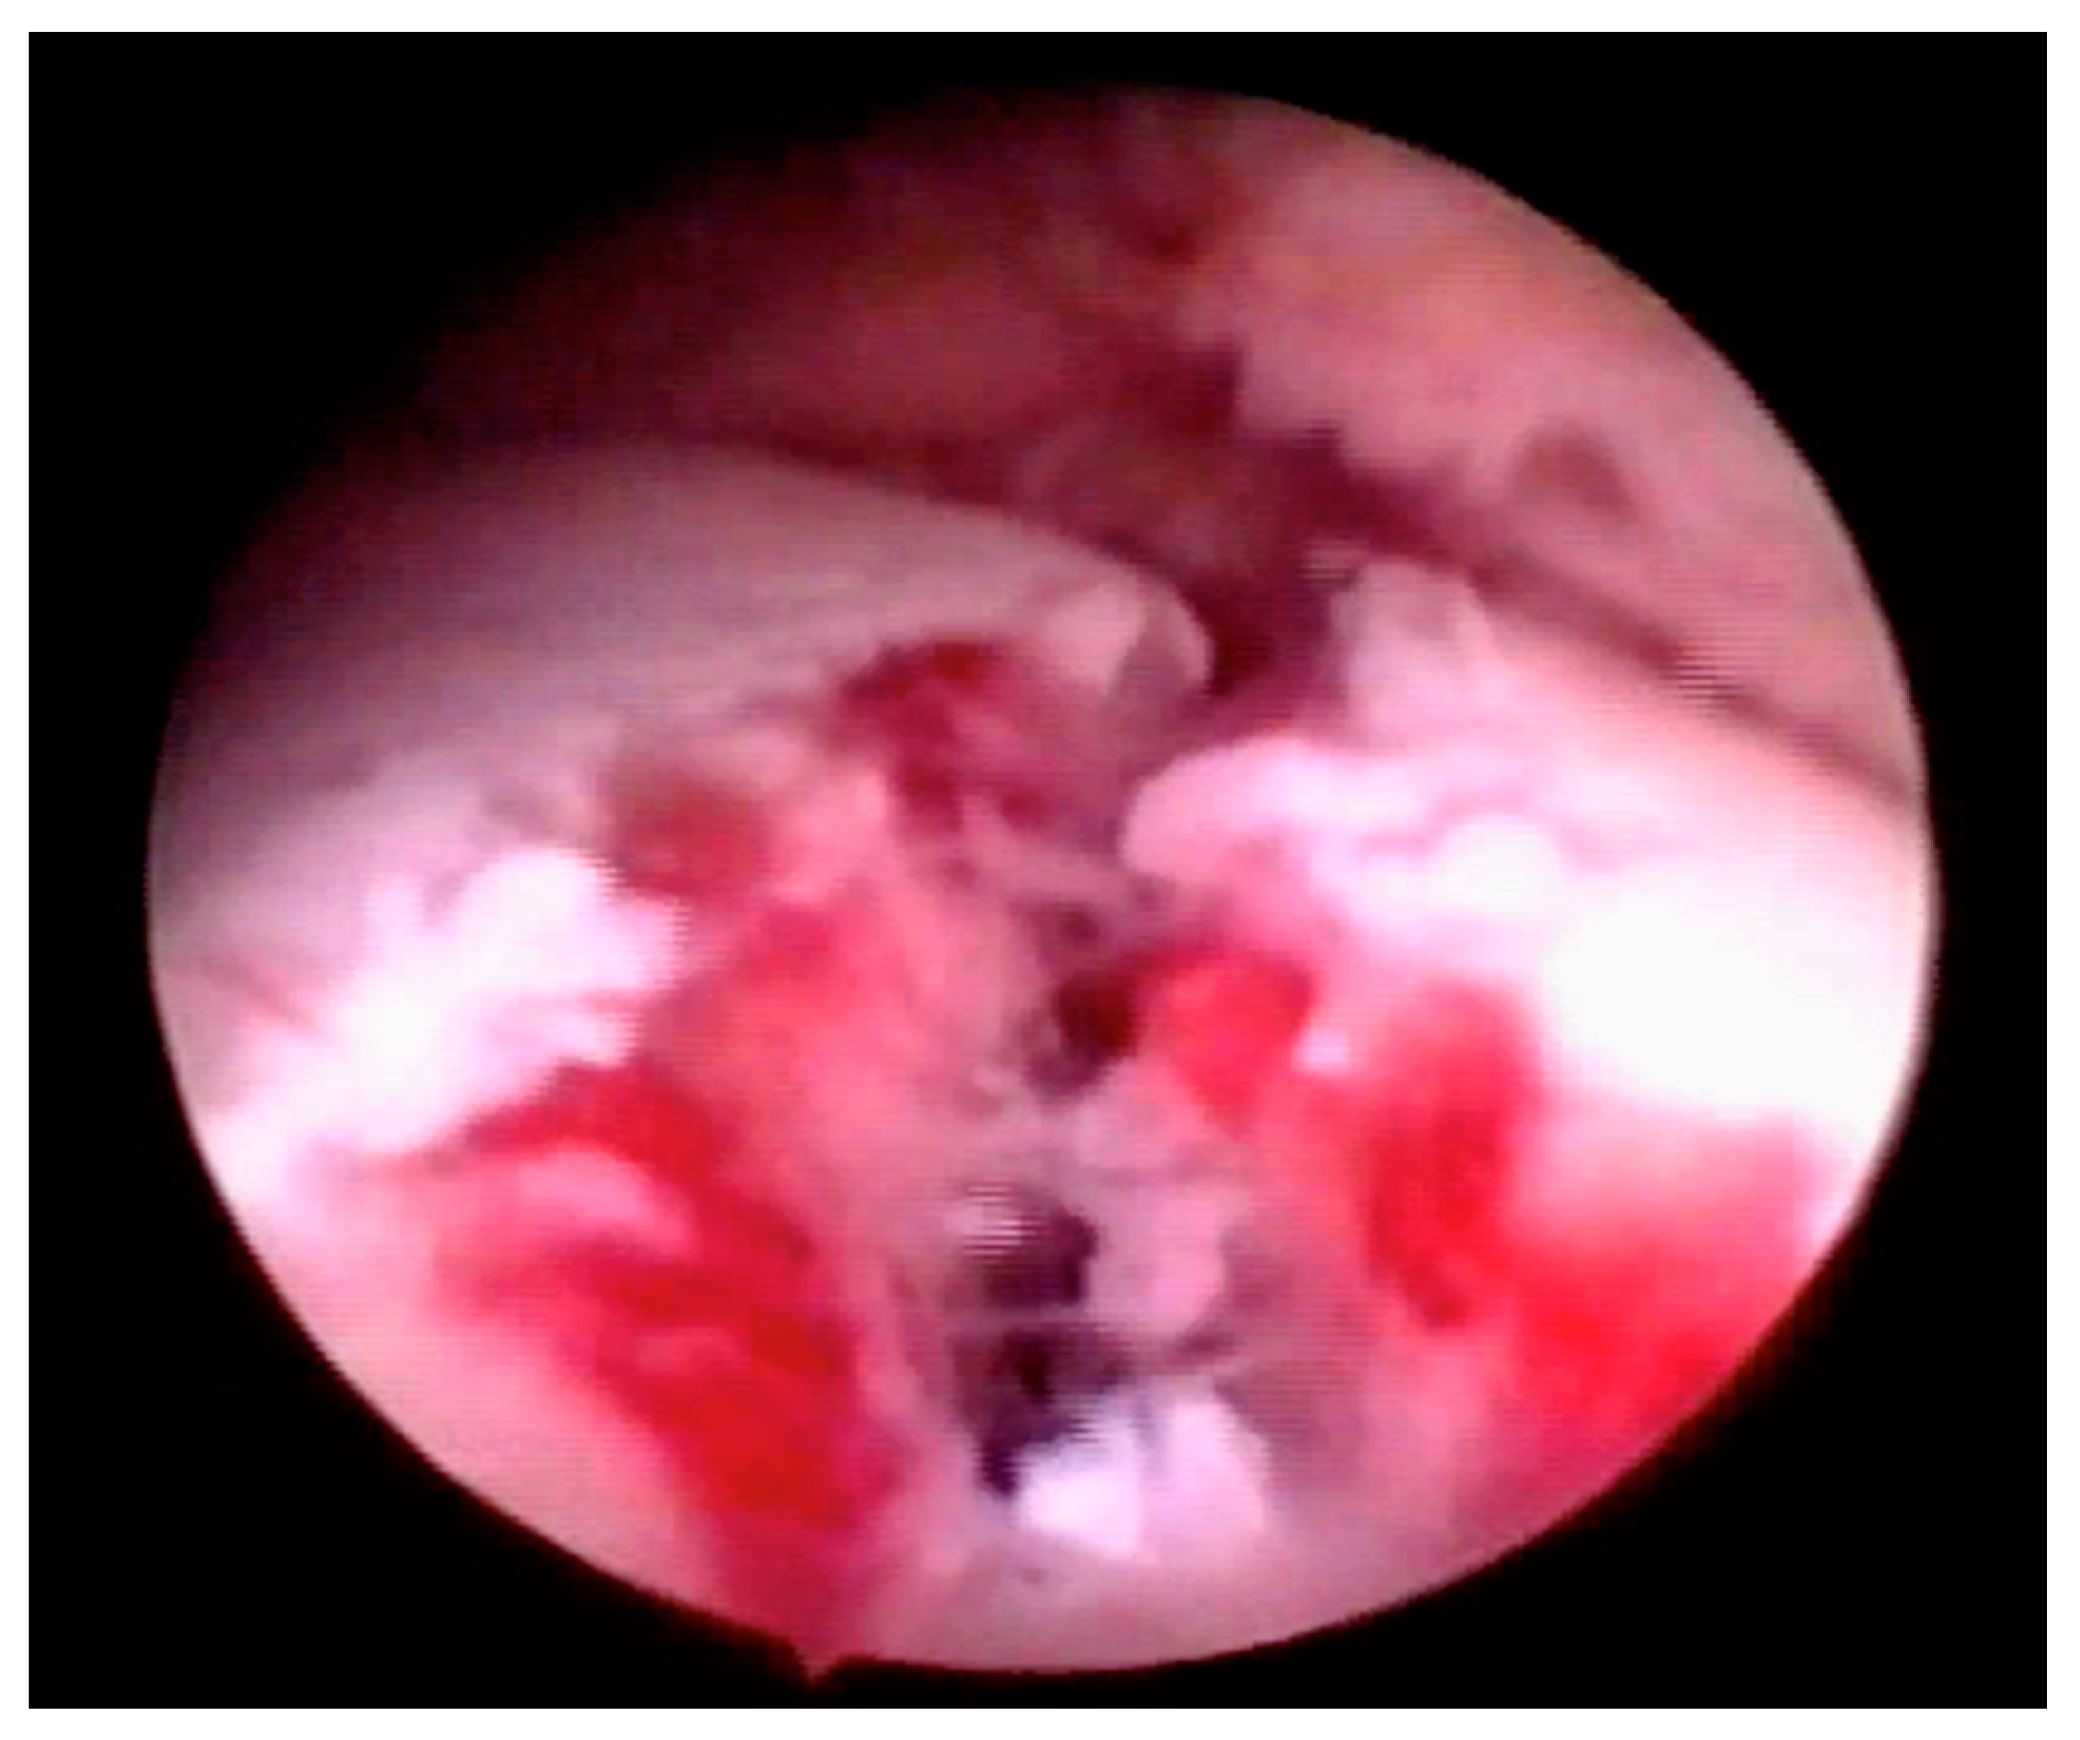

- Partial erosion of the articular surface (Figure 5)